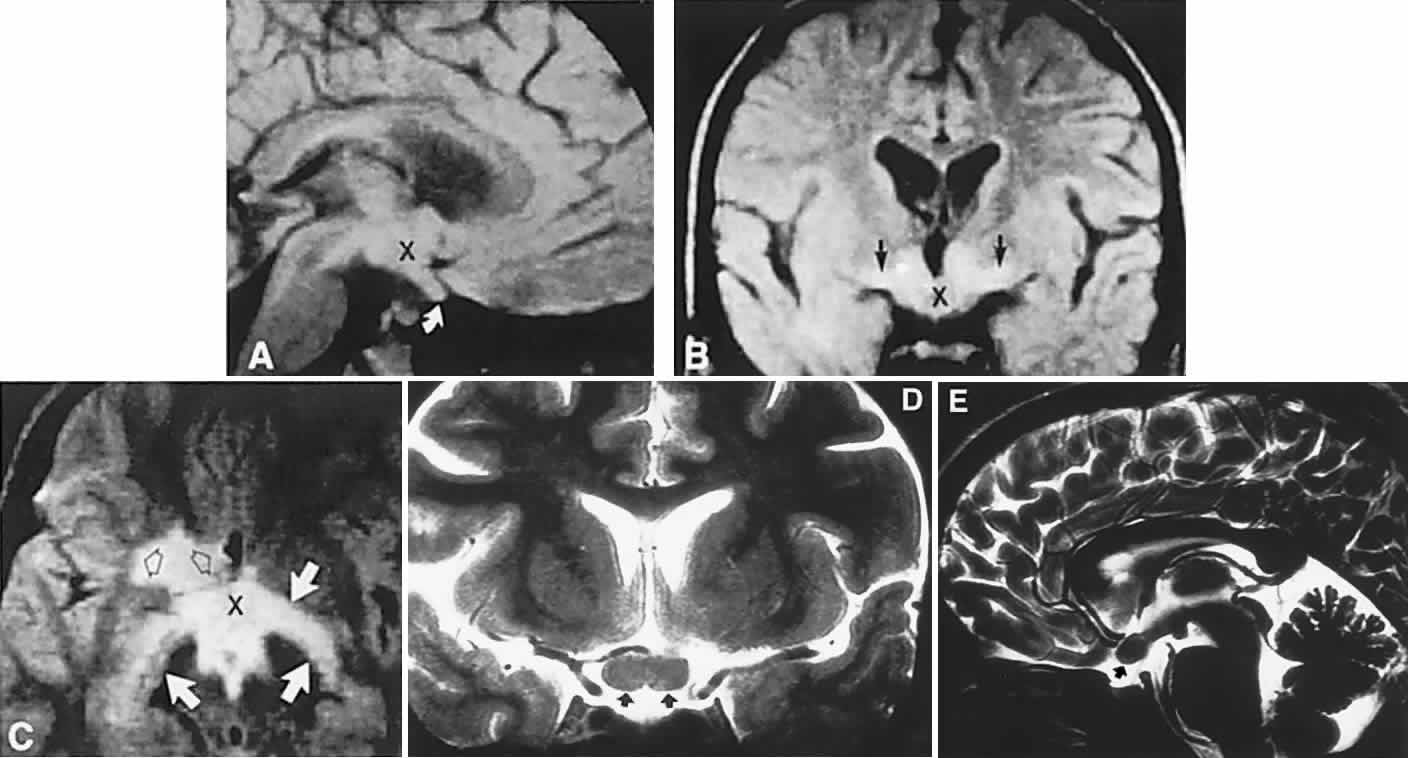

Fig. 3. Neuroimaging of pituitary adenomas. A. Axial computed tomography (CT) section shows a round tumor mass filling the suprasellar cistern; ring enhancement (arrows) indicates subcapsular hemorrhage. B. Contrast-enhanced coronal CT section through a large invasive adenoma. Note encasement of the carotid artery (arrows) and the position of the middle cerebral artery above (arrowheads). C. Axial CT section shows lateral expansion into the cavernous sinuses (white arrows) and a necrotic cyst (black arrow). D. Subfrontal superior extent of the mass. Note the middle cerebral arteries. E. Magnetic resonance imaging of a large lobulated prolactinoma, with suprasellar extension. Note the distortion of the third ventricle (open arrows) and extension toward the temporal lobe (long arrow); the tumor has not involved the sphenoidal sinus (s). F. Chiasm (arrowheads) is draped on the superior surface of the tumor (TR, 550 milliseconds; TE, 26 milliseconds). G. Sagittal section shows suprasellar growth with the chiasm above (arrowheads); the sella (arrows) and sphenoidal sinus (s) are normal (TR, 850 milliseconds; TE, 26 milliseconds). H. Hyperintense signal (TR, 2000 milliseconds; TE, 60 milliseconds) indicates the partial cystic character. Sagittal (I) and axial (J) sections with head tilt to the right, in case of a large cystic adenoma with an interface level between newer blood (white arrow) and older blood (black arrow) (TR, 800 milliseconds; TE, 30 milliseconds). K. Signal difference is intensified (TR, 2100 milliseconds; TE, 80 milliseconds). L. Hemorrhage (bright signal, arrow) in a pituitary adenoma with headache and bitemporal field depressions. M. Without interventions, 2-month follow-up showed spontaneous involution, with normal pituitary gland (arrow), stalk, and chiasm.